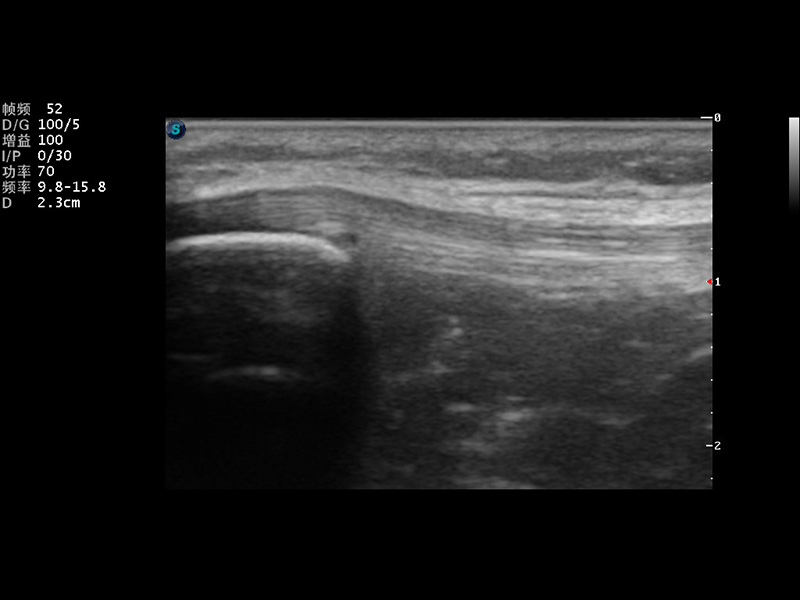

S9便携式彩色多普勒超声诊断仪是乐玩lewin国际研发的高端便携彩超设备,外观设计新颖、产品性能卓越。S9在便携超声领域采用了突破传统的触摸屏交互设计,并以先进的软件硬件技术和设计理念,为您带来清晰的图像质量、稳定的工作性能和便捷的操作体验。

VIS平台设计